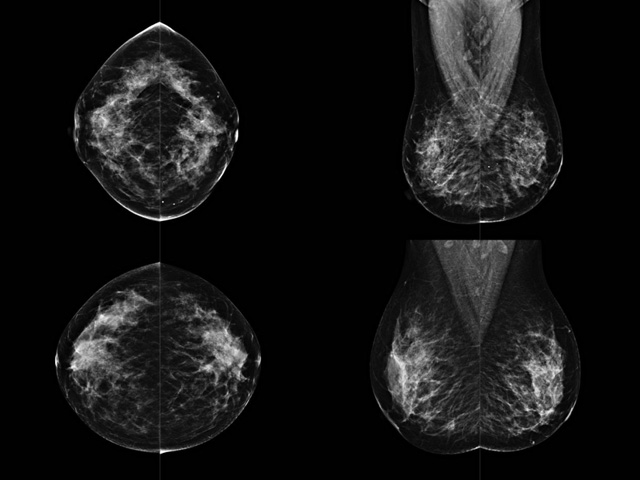

乳腺DR成像設(shè)備中非晶硅跟非晶硒兩種平板探測(cè)器

乳腺DR成像設(shè)備中非晶硅跟非晶硒兩種平板探測(cè)器。更要提供優(yōu)質(zhì)的圖像質(zhì)量乳腺的組織結(jié)構(gòu)與厚度各不相同,減少重拍率輻射劑量,,乳腺的主要構(gòu)成組織均為軟組織結(jié)構(gòu),組織之間密度十分相似,缺乏天然對(duì)比度。選擇軟X線攝影技術(shù)獲得良好對(duì)比度的乳腺結(jié)構(gòu)影像。增加各組織對(duì)X線的吸收差異。乳腺攝影測(cè)和分類,平板探測(cè)器的像素尺寸范圍應(yīng)在50到100μm之間。特別是微鈣化灶可以小到100到200μm,平板探測(cè)器都必極小微鈣化灶進(jìn)行成像。

乳腺DR是利用X光來做檢查,在一瞬間將被檢測(cè)到的位置投影出來,因?yàn)槭撬查g的輻射,所以只需要0.5秒的時(shí)間。因此對(duì)病人的輻射很低,大約是0.023mSv,比國(guó)家的標(biāo)準(zhǔn)要低得多。DR系統(tǒng)由 X線、發(fā)生裝置、直接轉(zhuǎn)換平板探測(cè)器、系統(tǒng)控制器、影像監(jiān)視器、影像處理工作站等組成。能檢查胸腔積液、肺結(jié)核、大葉性肺炎、肋骨骨折等。心室增大、主動(dòng)脈擴(kuò)張、主動(dòng)脈瘤等心臟病。腹部病變,如腸梗阻、腸穿孔等,DR上可見液氣平面、膈下游離氣腫。DR表現(xiàn)不正常,要結(jié)合臨床表現(xiàn)、體征、癥狀等綜合分析,結(jié)合CT、彩超、血液分析等,才能作出正確的判斷。